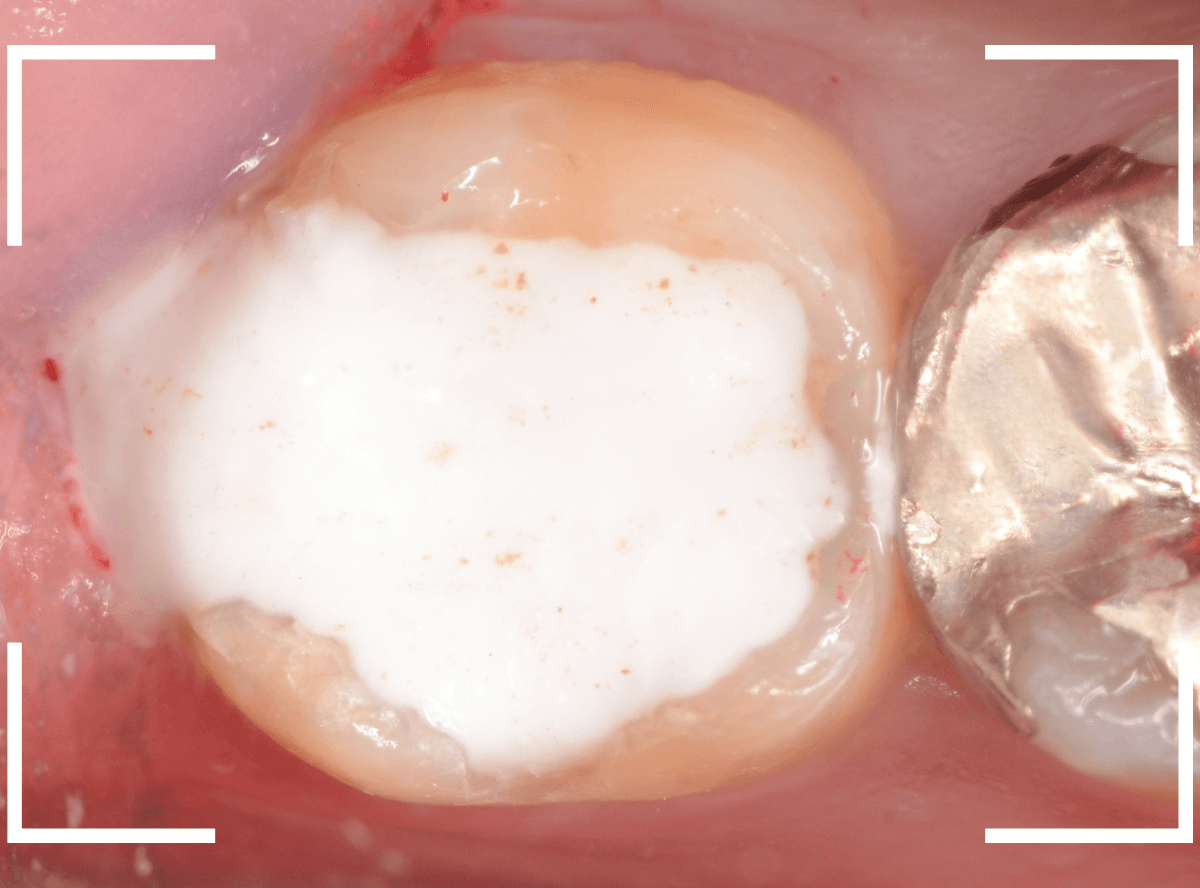

電気メスで、虫歯周囲の歯肉を除去後、全ての虫歯を除去しました。

虫歯は深かったですが、なんとか神経寸前のところで食い止められました。

神経を保護するお薬をつめて、セメントで蓋をしてしばらく経過観察します。

経過観察後、痛みがない事が確認できれば、つめものを作製します。